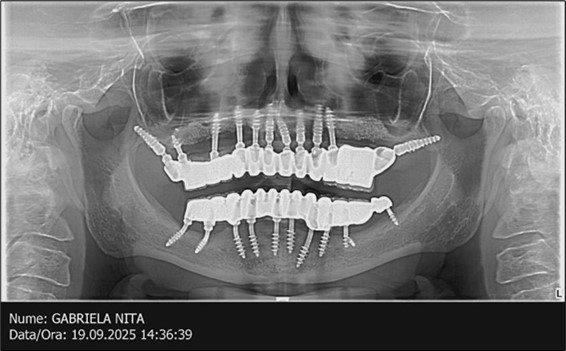

Figure 3.Panoramic pictures after removal of implants affected by peri-implantitis, extractions, alveolar crest regularization, and insertion of corticobasal and TPG implants (07.2022)

A total of 11 implants is placed in the maxilla, including compressive TPG implants with a polished surface in the maxillary-sphenoid fusion area (Figure 3, Figure 9). Similarly, in the anterior region, final fixation is achieved in the nasal cortex, and BCS corticobasal implants are added in areas with massive bone loss in the frontal region (Figure 3, Figure 8, Figure 11). Additionally, in the palatal sinus cortical area, with the aim of avoiding the addition and sinus lift zone where the second cortical bone no longer exists, 3 implants are placed, 2 in quadrant 1 and 1 in quadrant 2 (Figure 3, Figure 8). Through the Caldwell-Luc sinus lift procedure, the sinus cortical bone is displaced to allow the placement of the graft material and elevation of the sinus membrane. This sinus cortical is no longer recreated at the junction of the graft material and mucosa-sinus membrane, making it impossible to place a corticobasal implant, which relies on the second cortical bone. In the distal mandibular area, after the removal of two stage implants due to massive destruction in quadrant 3, implant placement distal to the mylohyoid line is not possible, as in quadrant 4 (Figure 10). A re-intervention occurs after 5 months to stabilize the area (Figure 12, Figure 14). Also, at the moment of fixation, the tip of one implant fractures, and the decision is made to leave it in place due to regional bone destruction, in order to avoid enlarging the bone defect.

In the interforaminal area (Figure 3, Figure 13), 6 corticobasal implants are also placed. The increased number of implants is due to the poorly represented distal area that needs to be compensated.